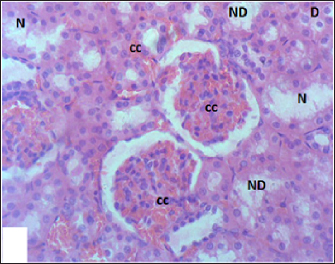

Mouse liver from the control group shows a normal radiant arrangement of the hepatic cells (Fig. 1). Pathological changes in treated liver sections showed an increase in the immune cells’ infiltration, and marked congestion were observed in almost all mice. In group 1, there was hemorrhage, congestion, and degenerated cells (Fig. 2). In group 2, there was congestion of the central vein, infiltration of immune cells, and degeneration of hepatocytes (Fig. 3). Whereas in group 3, the previously mentioned changes were markedly intensified with severe hemorrhage and marked sinusoidal dilatation (Fig. 4). Mouse kidney of control group shows normal cellular appearance (Fig. 5); however, pathological changes in treated kidneys sections reveals congestion, tubular necrosis and cast in some tubule’s lumen, group 1 (Fig. 6). In group 2, there was congestion, tubular necrosis, necrotic debrites in the tubuli lumen and cast (Fig. 7). Whereas in group 3 there was marked congestion, tubular and cellular necrosis, necrotic debrites in the tubular lumen and degenerated cells (Fig. 8).

Fig. 8. Section of mouse kidney fed with 3 mg/kg Lorazepam showing marked congestion (cc), tubular and cellular necrosis (N), necrotic debrites in the tubuli lumen (ND) and degenerated cells (D), (H and E, ×400).